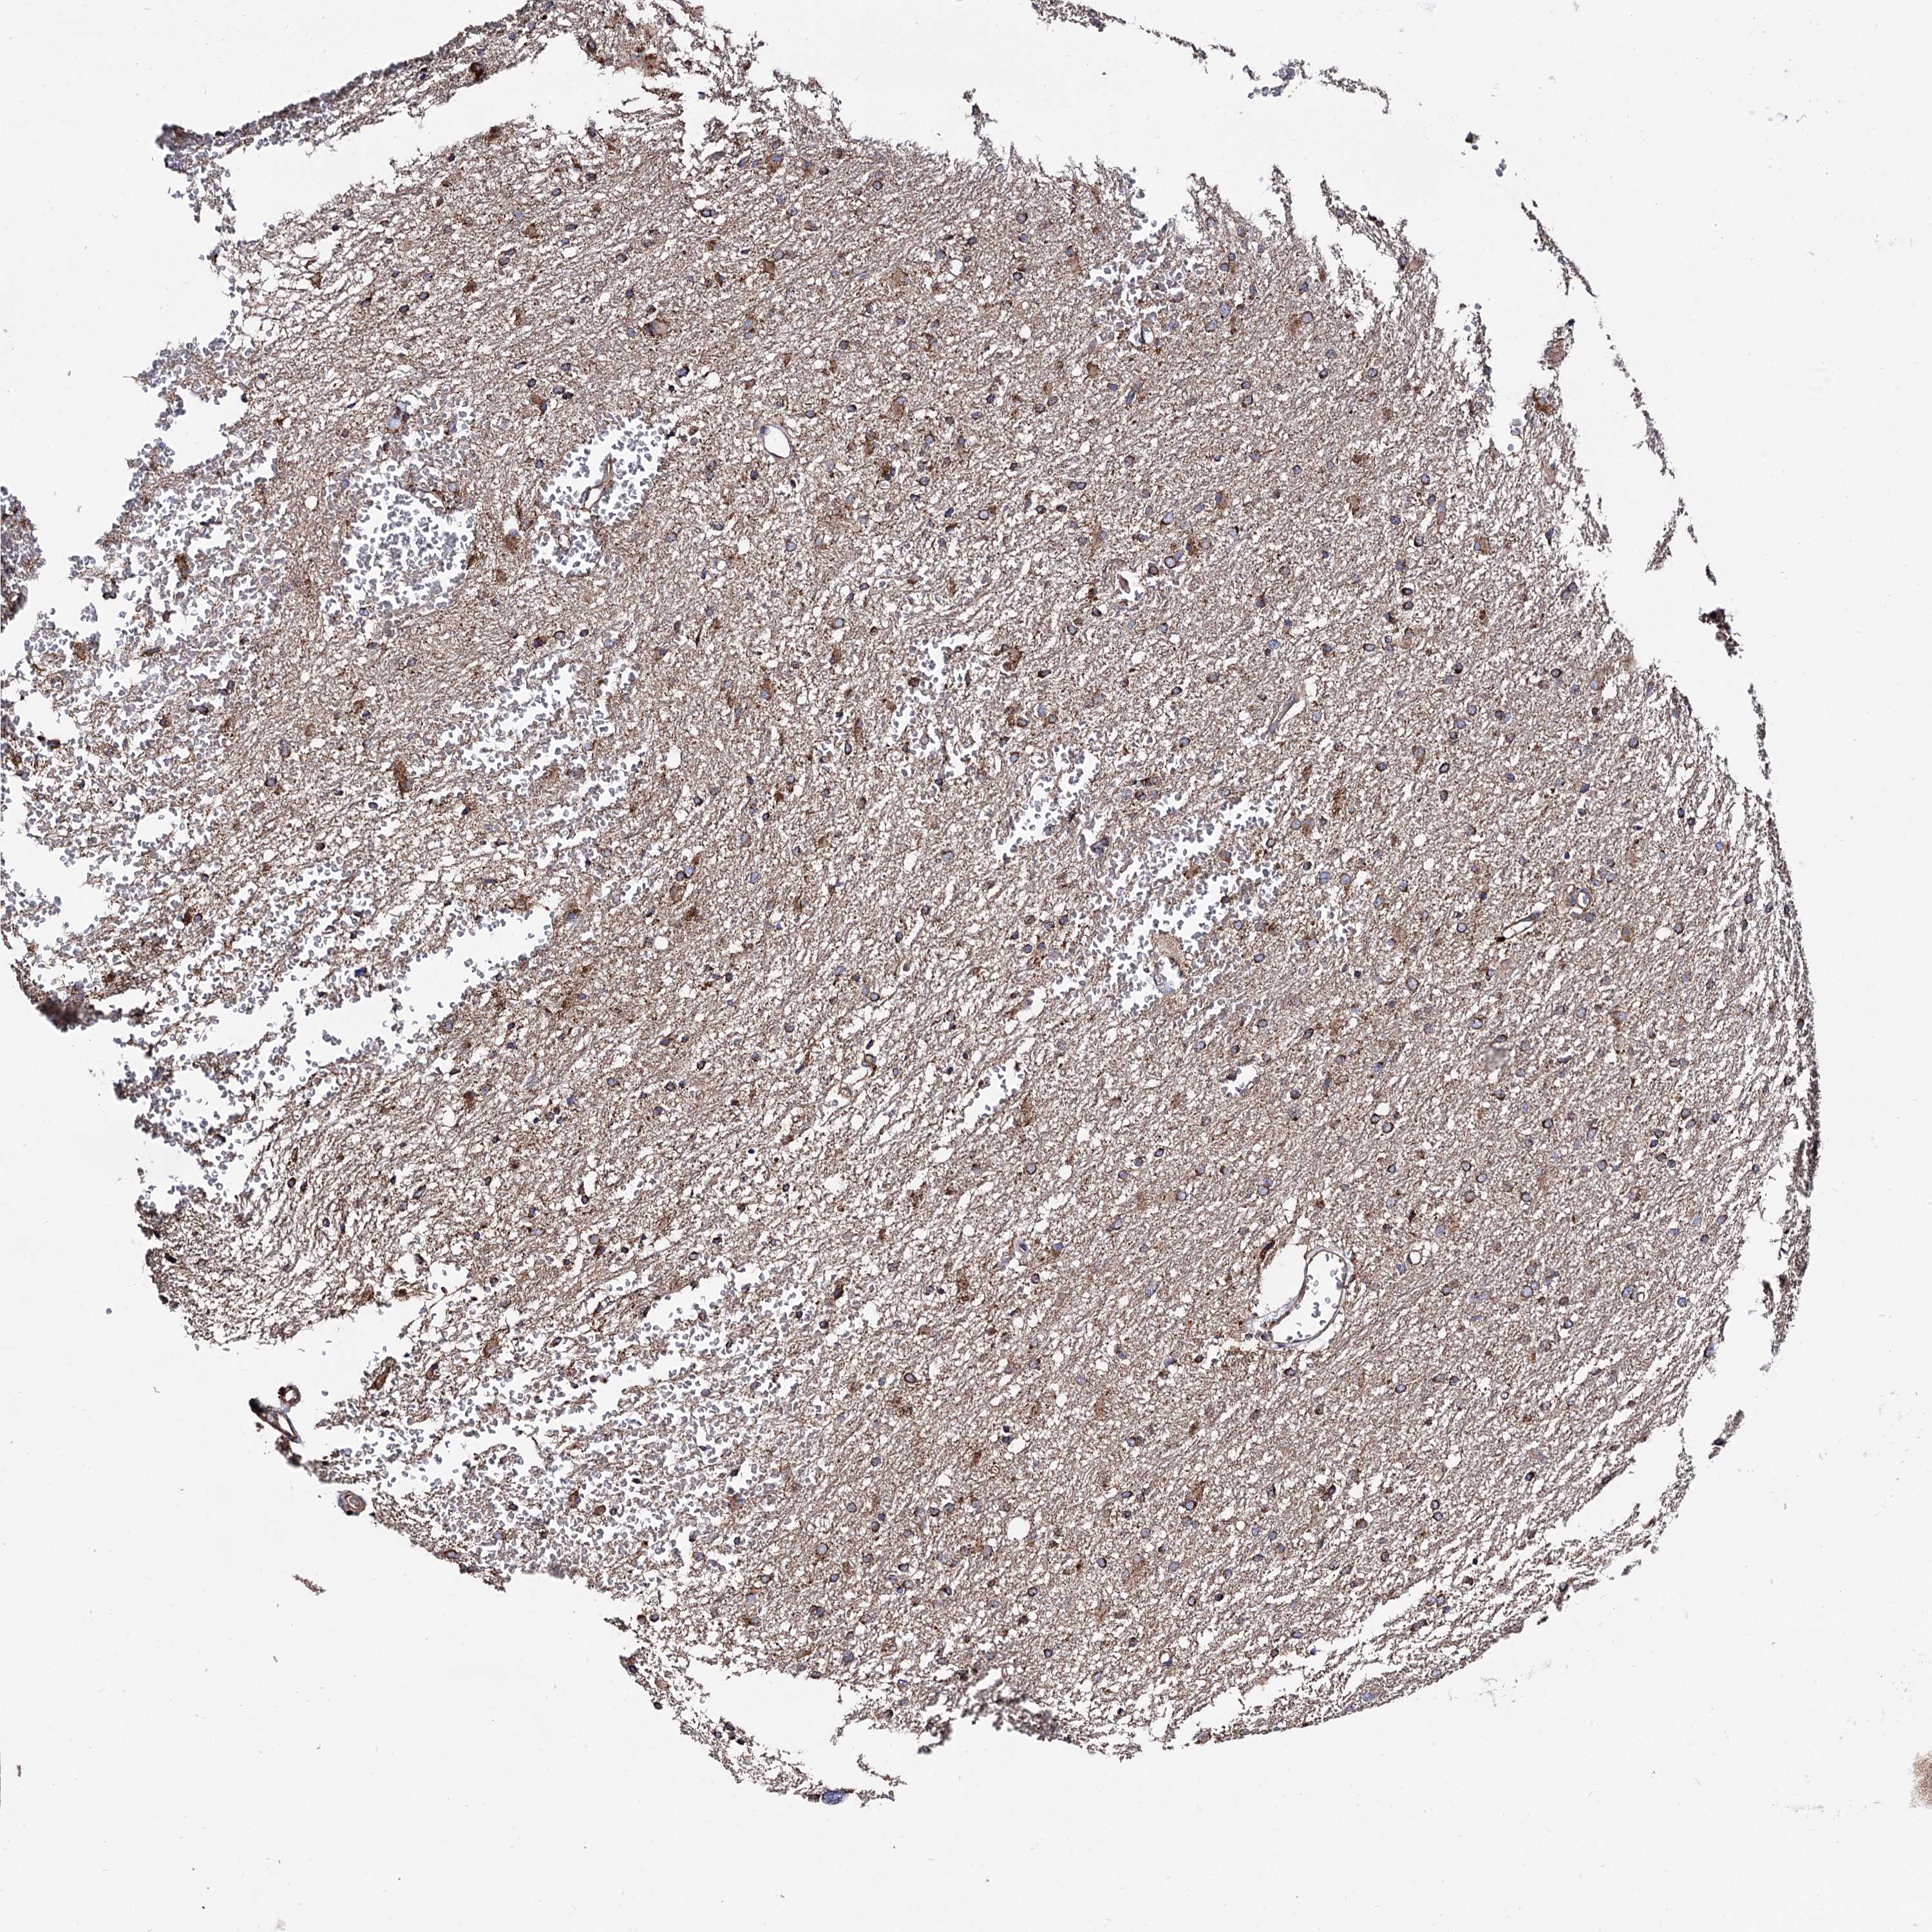

GLIOMA - Protein expressioni

A mouse-over function shows sample information and annotation data. Click on an image to view it in a full screen mode. Samples can be filtered based on level of antibody staining by selecting one or several of the following categories: high, medium, low and not detected. The assay and annotation is described here.

Note that samples used for immunohistochemistry by the Human Protein Atlas do not correspond to samples in the TCGA dataset.

Antibody stainingi

Antibody staining in the annotated cell types in the current human tissue is reported as not detected, low, medium, or high, based on conventional immunohistochemistry profiling in selected tissues. This score is based on the combination of the staining intensity and fraction of stained cells.

Each image is clickable and will lead to virtual microscopy that enables deeper exploration of all samples and also displays staining intensity scores, fraction scores and subcellular localization as well as patient and tissue information for each sample.

Antibody HPA040845

Staining

High

Medium

Low

Not detected

Intensity

Strong

Moderate

Weak

Negative

Quantity

>75%

75%-25%

<25%

None

Location

Nuclear

Cytoplasmic/membranous

Cytoplasmic/membranous,nuclear

Glioma, malignant, High grade

Glioma, malignant, Low grade